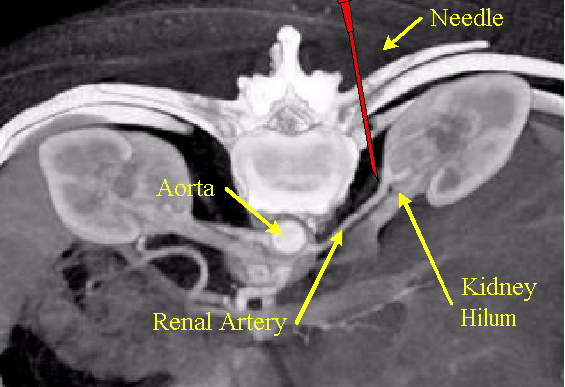

Mark和我为此目的专程来中国,与上海和某个省会城市的三甲医院心内科主任交流探讨开展这一临床研究的可能性。上海这家医院的主任考虑到这一研究的新颖性和侵入性,以院方伦理可能难以批准为由,婉拒了合作。最后我们与那家省城医院的心内科主任达成了合作签订了合作协议,提供了研究经费以及给他个人的专家顾问咨询费。在确定了临床方案,通过了医院的伦理后,2005年的一月份,Dr. Howard Levin,Hanson Gilford,Dr. Joshua Weintraub和我从美国飞来中国,与国内医生一道,为两例病人施行了在CT引导下穿刺至肾门注射丁哌卡因的手术(图2)。之后由国内医生独立施行这一术式,到2005年三月底又陆续完成了五例病人,需要指出的是入选的都是心衰病人。

图2 从腰后侧CT引导穿刺注射Marcaine, 阻滞肾神经